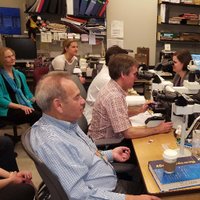

#neuropathology conference with the #LivingLegend Dr. J.L Perez-Berenguer Today's topic: Astrocytic lesions/tumors #pathology #neuropath #neuro #residentlife #PerezBerenguer Karra Jones, MD, PhD Fausto Rodriguez AANP Hopkins Neuropath